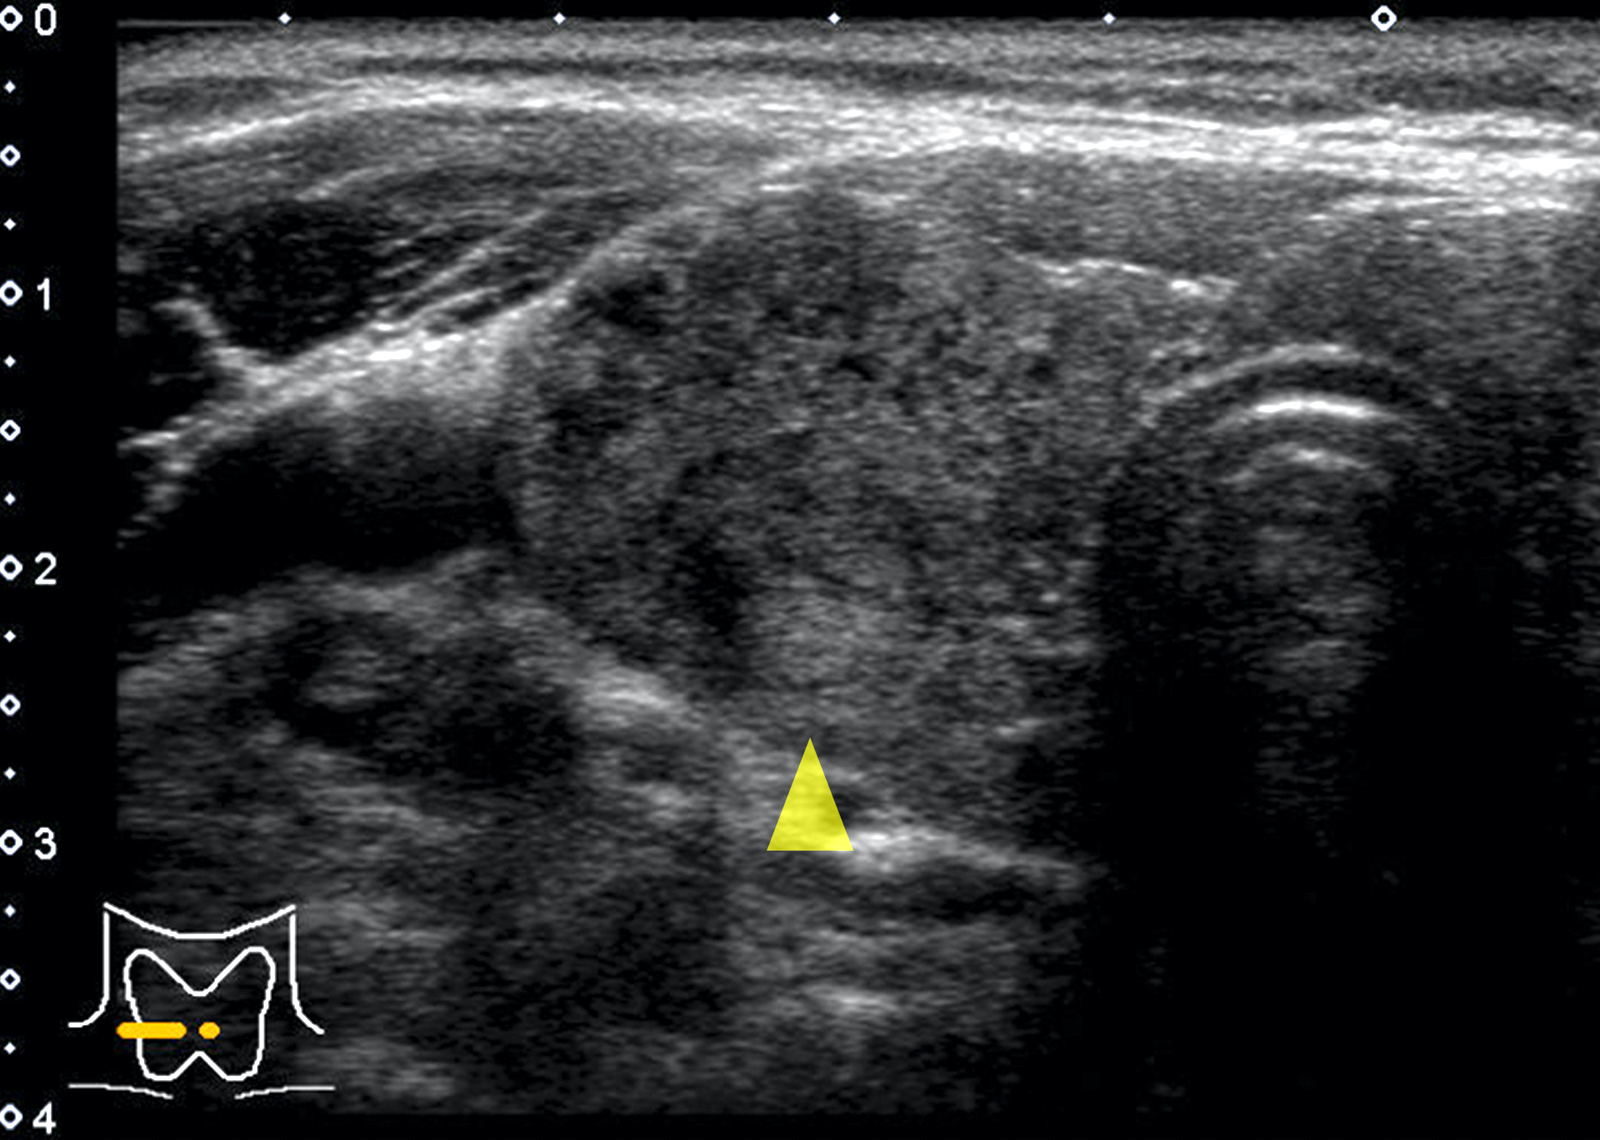

Radiology description

- Sonography: diffusely enlarged thyroid gland; diffusely heterogeneous, coarse and hypoechogenic parenchyma with micronodular pattern (Eur J Endocrinol 2019;181:539, AJR Am J Roentgenol 2010;195:208)

- IgG4 related variant: more marked hypoechogenicity (Autoimmun Rev 2014;13:391)

- Fibrous variant: hypoechogenicity along with prominent nodularity of the parenchyma

Radiology images